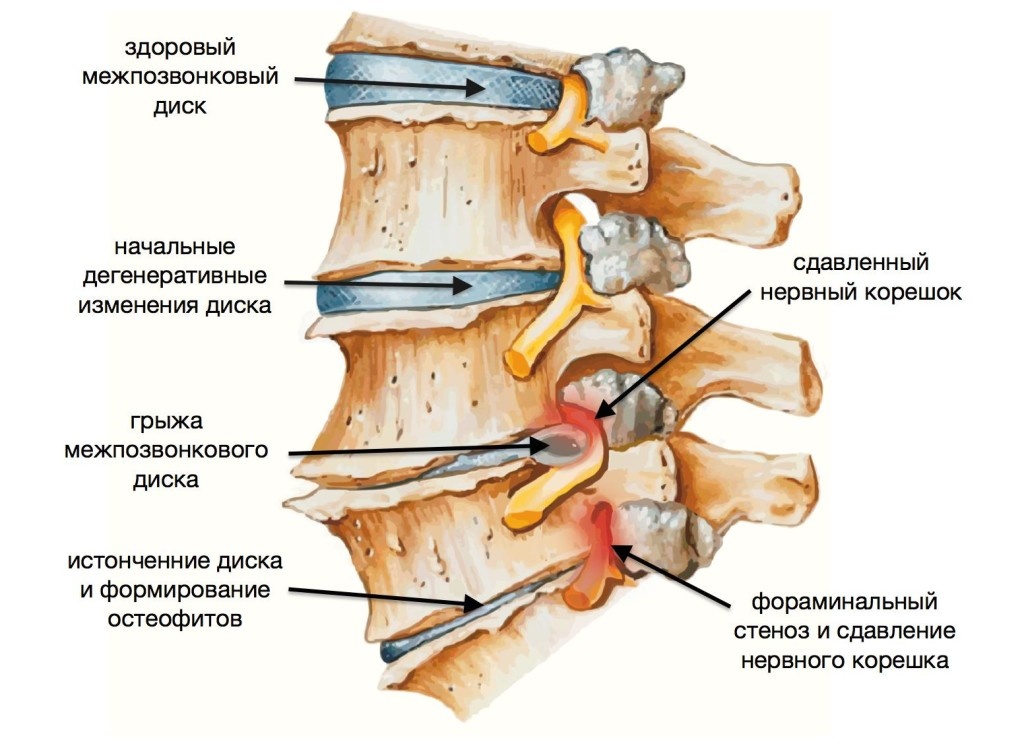

Структура и анатомия синдесмоза: научные иллюстрации